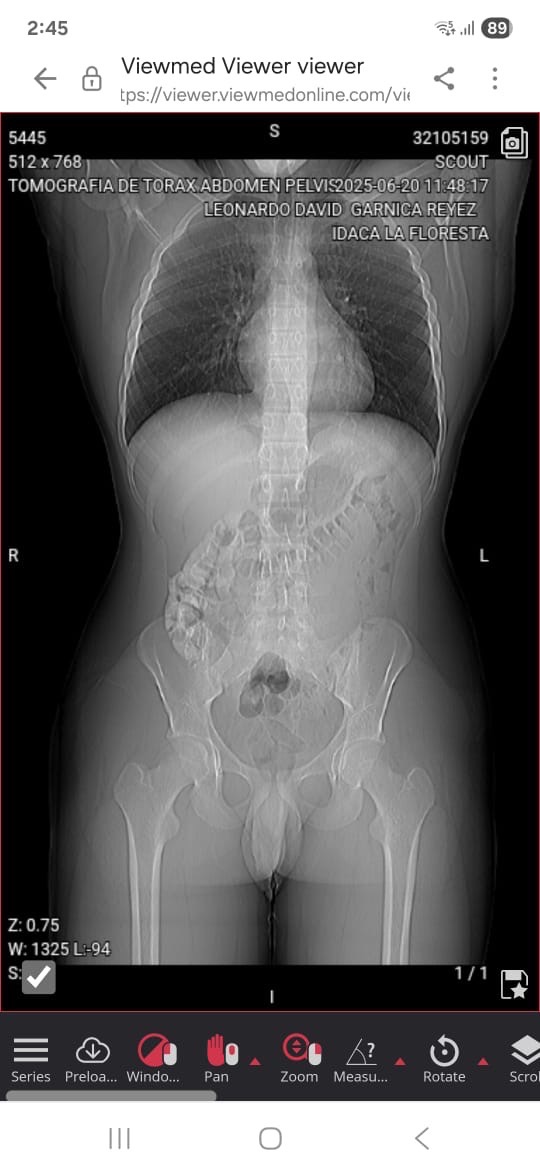

actualmente me encuentro pasando un momento difícil, ya que me diagnosticaron células cancerígenas mixtas en el testículo izquierdo.

Fui intervenido quirurgicamente el procedimiento realizado fue: orquidectomia radical izquierda para extraer un tumor seminomatoso mixto , sin embargo a pesar de haber sido atendido a tiempo y cambiar mi futuro completamente por las consecuencias que provienen de este procedimiento los marcadores tumorales continúan elevados por lo que voy a tener ser sometido a tratamiento de quimio terapias.